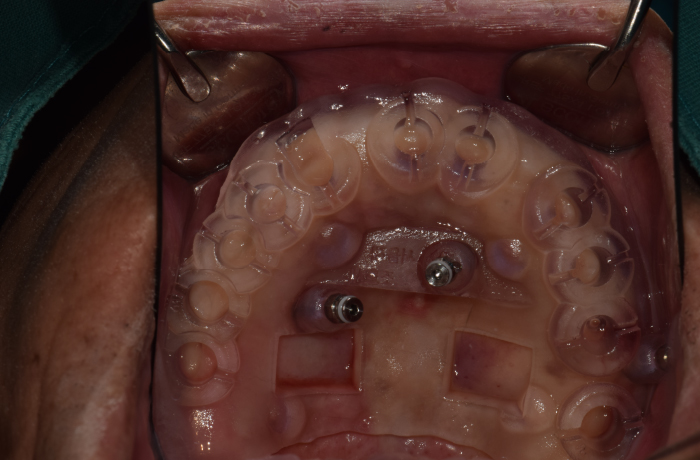

구강스캔 Serec Omnicam , One Scan

• Cerec Omnicam

환자 카운셀링 모드로 연속적인 3D 영상 지원으로 환자의 상태를 생생하게 보여주고 환자의 구강 데이터 전송 후 자동으로 임플란트 보철물을 15분 이내에 만들어 주기 때문에 빠른 치료가 가능한 인체공학적인 치과용 영상저장 전송장치 입니다. 기존 임플란트 제작 시 필요했던 본뜨기 작업이 불필요 해지므로 보다 더 빠르고 정확한 보철물 제작이 가능합니다.

• One Scan

구강 내 직접 스캔으로 더욱 정확한 치아의 배열과 교합 상태를 확인하고 원캐드 소프트웨어로 정보를 입력하는 구강스캐너입니다. 타 치과에 흔치 않은 자체기공소 보유로 보통 본을 뜨고 보철물 제작에 소요되는 하루 이상의 시간을 획기적으로 축소, 보철물 제작 시간이 15분 밖에 걸리지 않으며 임시치아가 필요하지 않기 때문에 최소 내원이 가능하여당일에 임플란트 치료가 가능합니다.